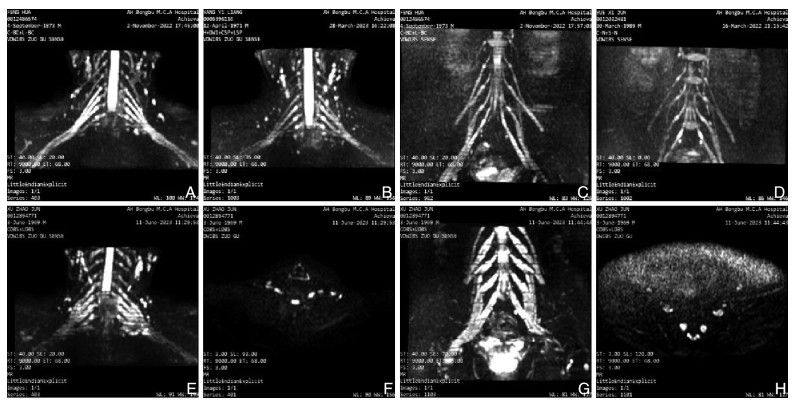

The clinical study of Bushen Huoxue Decoction combined with unilateral biportal endoscopy (UBE) in the treatment of lumbar spinal stenosis with kidney deficiency and blood stasis

E Yuan, HUANG Shengchang, RUI Lining

2025, 23(10): 1764-1767. doi: 10.16766/j.cnki.issn.1674-4152.004224

72 3

Abstract:

Objective  To evaluate the effects of Bushen Huoxue Decoction combined with unilateral biportal endoscopy (UBE) in patients with lumbar spinal stenosis (LSS) of kidney deficiency and blood stasis, focusing on recovery, inflammatory response, and postoperative complications, and to explore the therapeutic effect of integrated Chinese and Western medicine.  Methods  From June 2023 to April 2024, 120 patients with kidney deficiency and blood stasis type LSS were enrolled at Wujin Hospital of Traditional Chinese Medicine, Changzhou, and randomly divided into a treatment group (Bushen Huoxue Decoction + UBE) and a control group (UBE alone). The indicators such as visual analogue scale (VAS) score, Oswestry disability index (ODI) score, changes of serum interferon-γ (IFN-γ)/ interleukin-1α (IL-1α) were assessed.  Results  The treatment group demonstrated a higher overall response rate compared with the control group [86.67% (52/60) vs. 71.67% (43/60), χ2=4.093, P=0.043]. The VAS score in the treatment group was lower than that in the control group at 2 weeks and 1 month postoperatively (P < 0.05), while ODI score was lower at 1 and 6 months (P < 0.05). After treatment, serum IFN-γ and IL-1α levels in peripheral blood were significantly reduced in the treatment group compared with the control group (P < 0.05). The incidence of postoperative complications was also lower in the treatment group [6.67% (4/60) vs. 23.33% (14/60), χ2=6.536, P=0.011].  Conclusion  Bushen Huoxue Decoction combined with UBE can significantly improve the efficacy of kidney deficiency and blood stasis type LSS, reduce postoperative VAS and ODI scores, decrease serum IFN-γ and IL-1α levels, and reduce the risk of postoperative complications, supporting its value as an integrated therapeutic strategy.